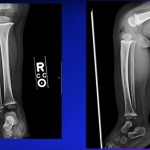

- Growth Plate vs Fracture (X-ray Differentiation)

| Feature | Growth Plate (Apophysis) | Fracture |

| Direction | Parallel to metatarsal | Perpendicular / transverse |

| Age | Appears: ~9 yrs | Any age |

| Closure | Girls: ~12 yrs, Boys: ~14 yrs | — |

| Edges | Smooth | Sharp, irregular |

Key exam point:

If line is parallel – normal apophysis

If transverse – fracture

- Radiological Landmark for Jones Fracture

- If fracture line:

- Toward cuboid Pseudo-Jones (stable)

- Between 4th & 5th MT – True Jones (unstable)

- Growth plate = parallel line

- Fracture = perpendicular line